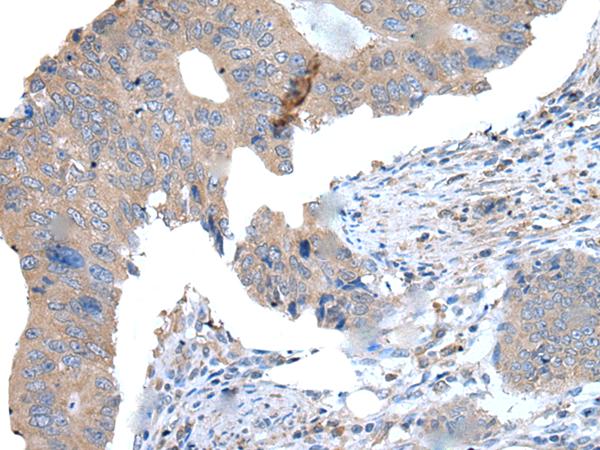

分类: 科研抗体货号: P12854别名: JEDI; MEGF12应用: IHC反应种属: Human, Mouse